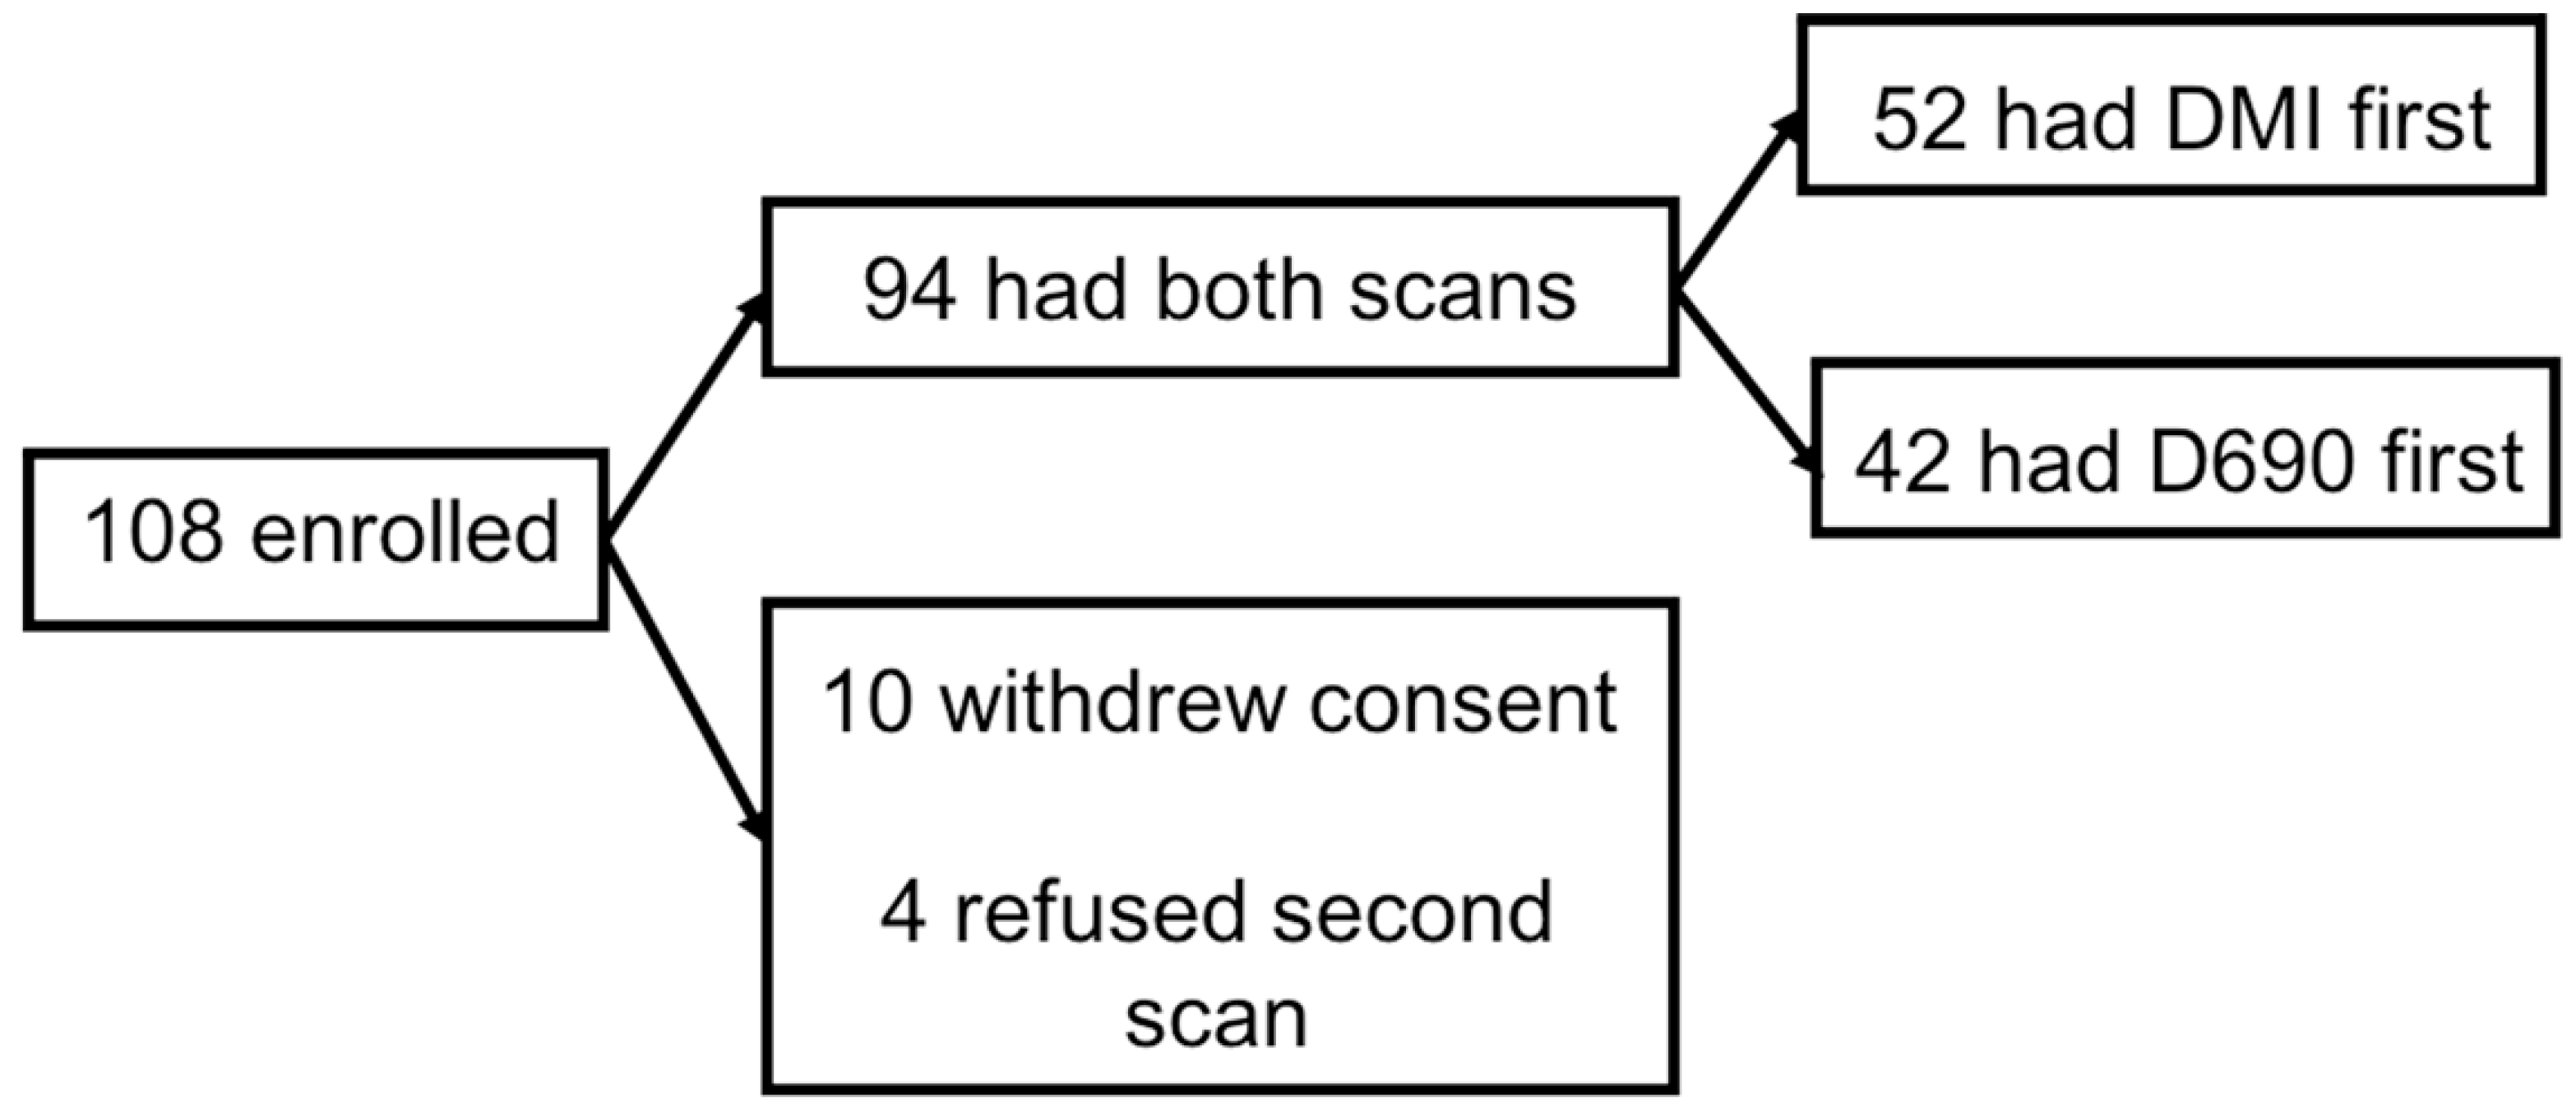

2.1. Participants

3.1. Patients’ Characteristics and PET Findings for the Entire Cohort

3.2. Results When SiPM PET/CT Was Used First Followed by Conventional PET/CT

3.3. Results When Conventional PET/CT Was Used First Followed by SiPM